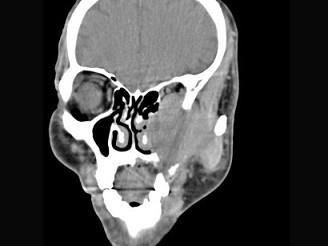

男,65岁,左眼球突出近一年,鼻涕带血,面颊部隆起,同时面颊部有麻木感,CT检查如图,最可能诊断为 ( )